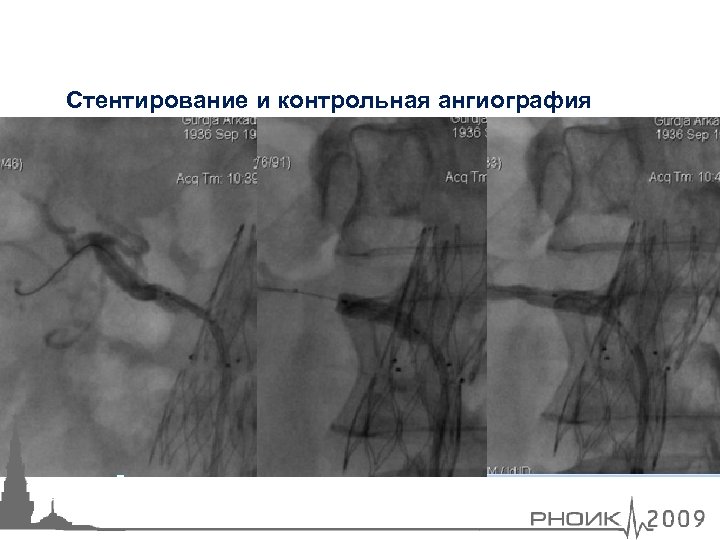

Стентирование и контрольная ангиография

Стентирование и контрольная ангиография